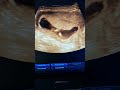

الجنين في السنة الأولي جنين يبلغ 11اسبوع فقط بجودة عالية ولأول مرة

الاسبوع الحادي عشر من الحمل وشكل الجنين بالسونار واعراض الحمل في الأسبوع ١١ ونصائح للمرأة الحامل

مراحل تكون الجنين من السادس إلى الأسبوع الثاني عشر

نمو الجنين في الاسبوع الحادي عشر من الحمل

الاسبوع الحادي عشر من الحمل اي شهر اعراض الحمل في الاسبوع الحادي عشر الاسبوع 11 من الحمل اي شهر